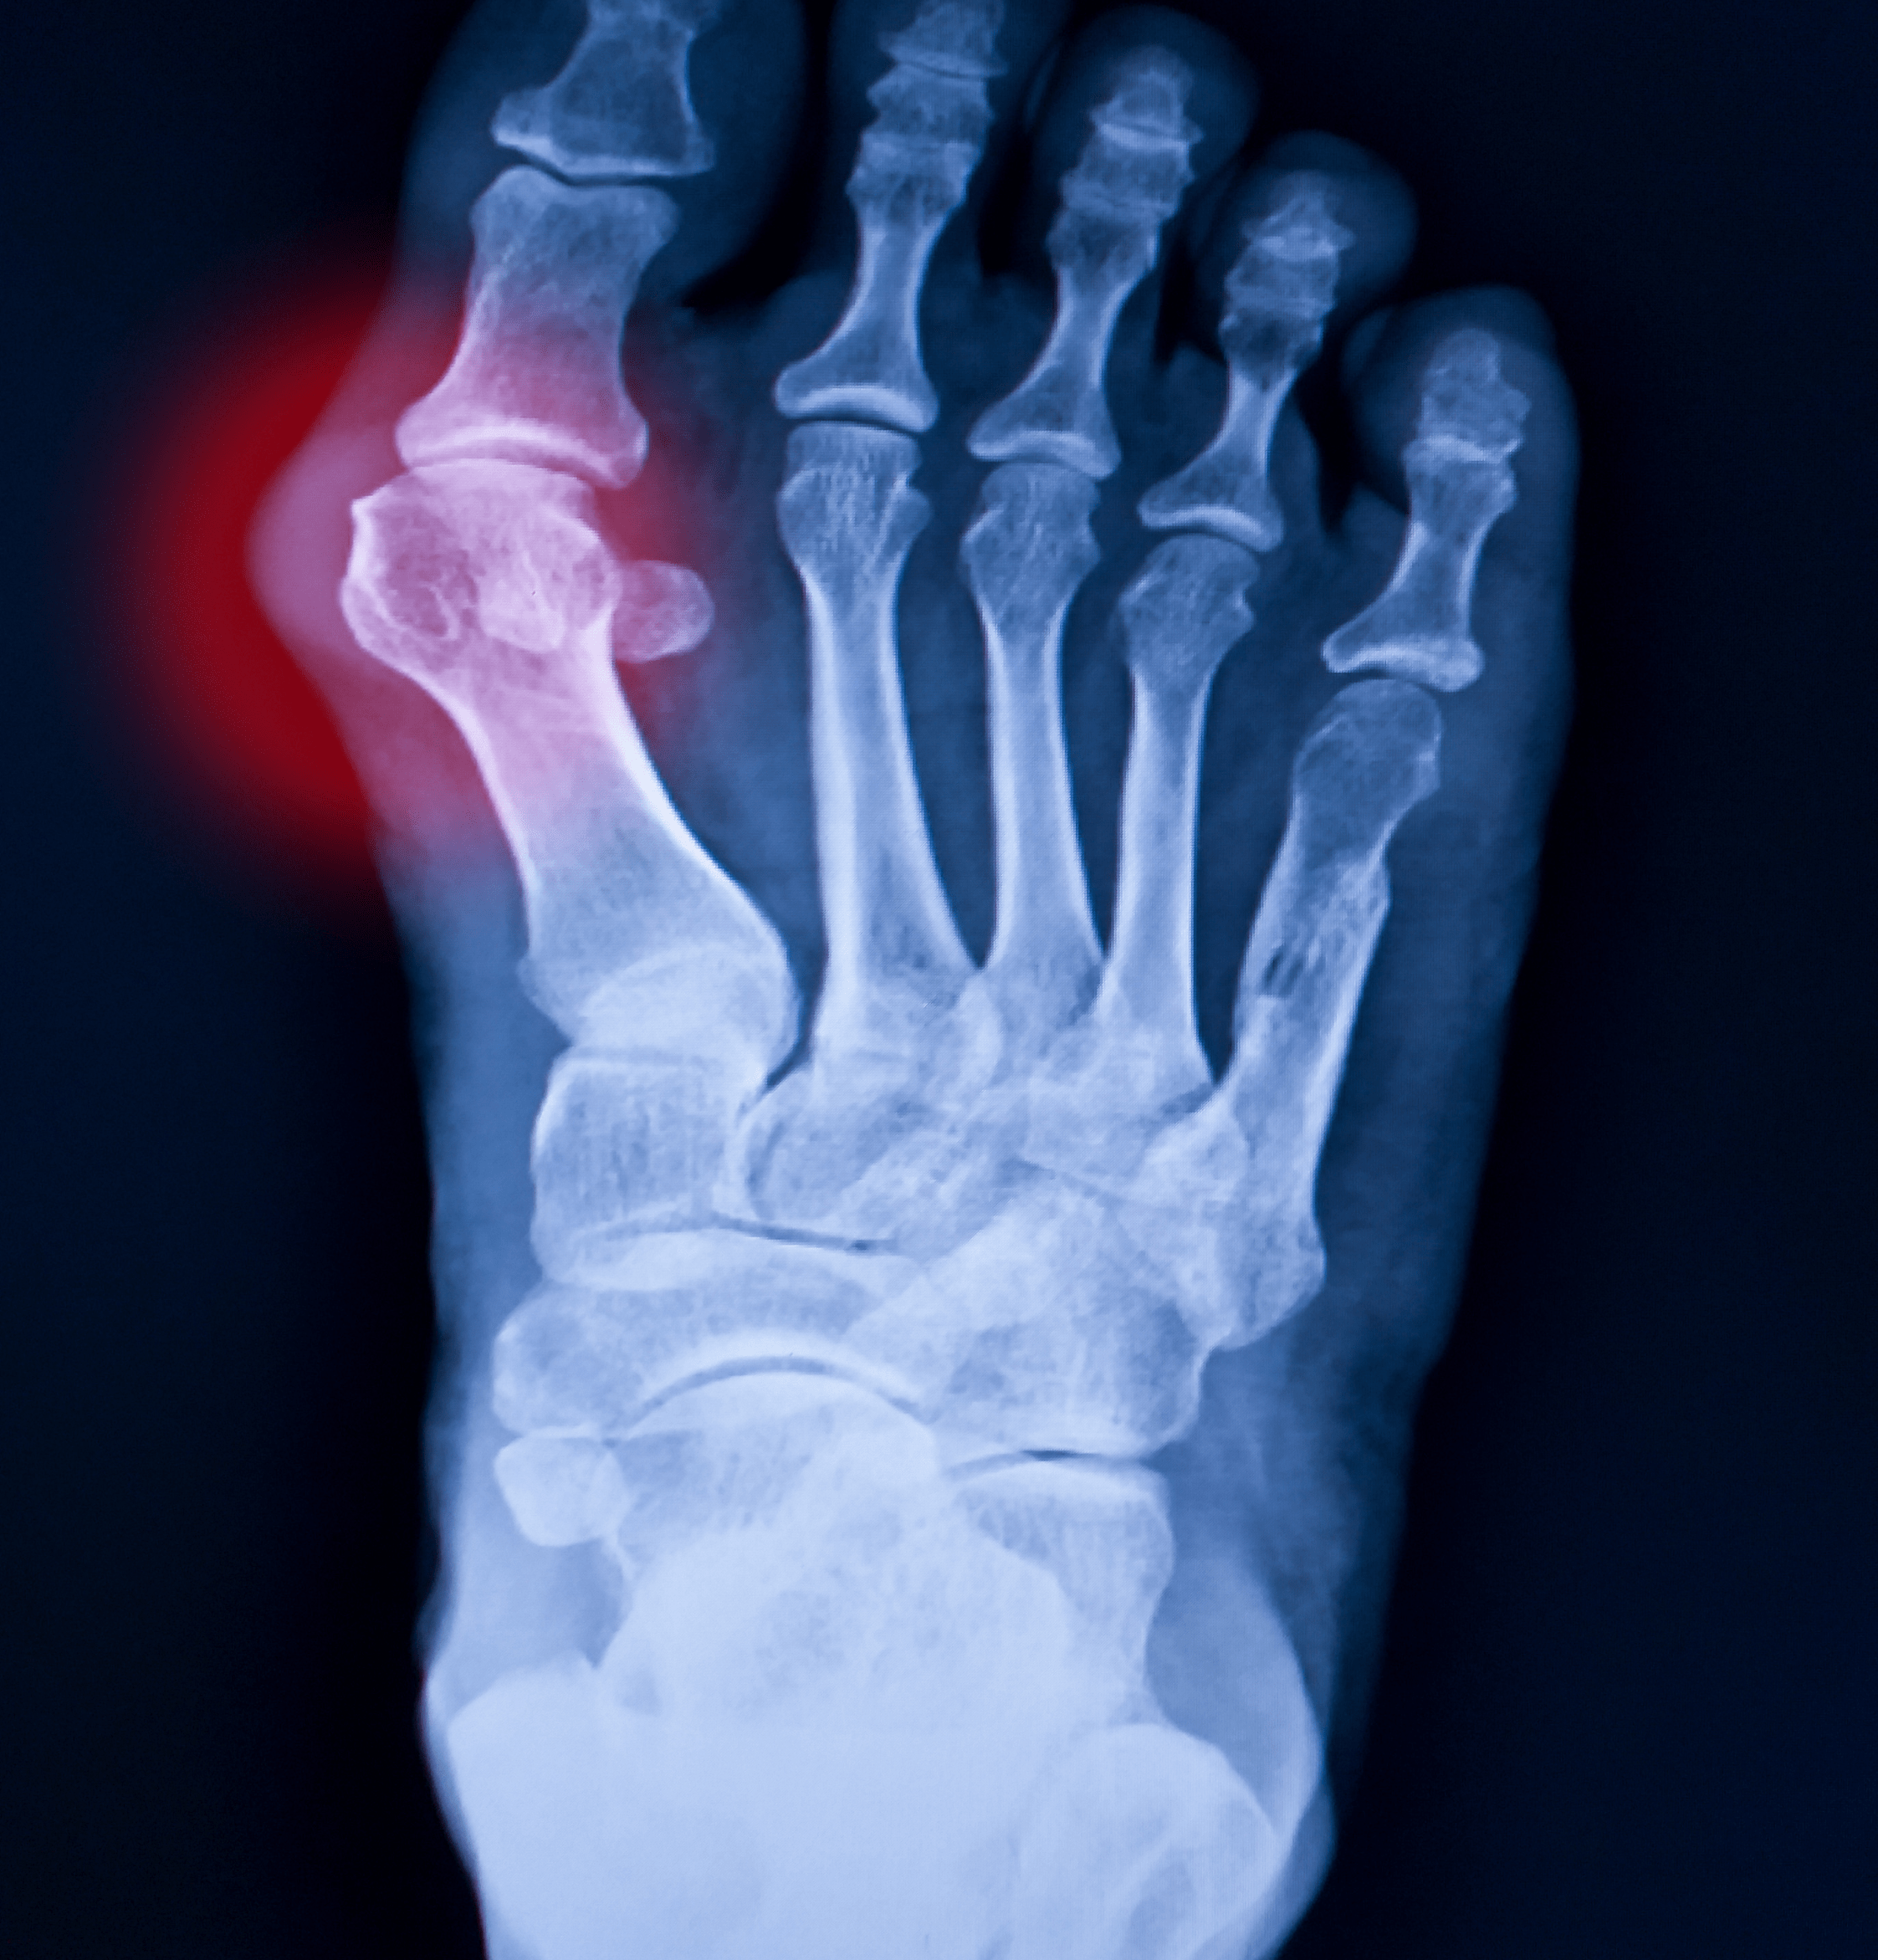

Radiografia piede

Che cos'è la Radiografia del Piede?

La radiografia del piede, o RX piede, è un esame diagnostico che utilizza i raggi X per creare immagini dettagliate delle strutture ossee del piede.

Questo esame permette di visualizzare le ossa del piede, che appaiono chiare rispetto ai tessuti molli circostanti.

L'esame viene eseguito posizionando il piede su un'apparecchiatura radiografica che emette raggi X, che attraversano il piede e creano un'immagine fotografica delle sue strutture interne.

A cosa serve la Radiografia del Piede?

La radiografia del piede è utilizzata principalmente per diagnosticare fratture, lussazioni, deformità ossee, artrite e altre patologie che possono colpire le ossa del piede

È uno strumento diagnostico fondamentale per valutare lesioni acute o croniche e monitorare il processo di guarigione delle fratture.

Inoltre, può aiutare a individuare eventuali anomalie strutturali o malformazioni che potrebbero causare dolore o problemi funzionali.